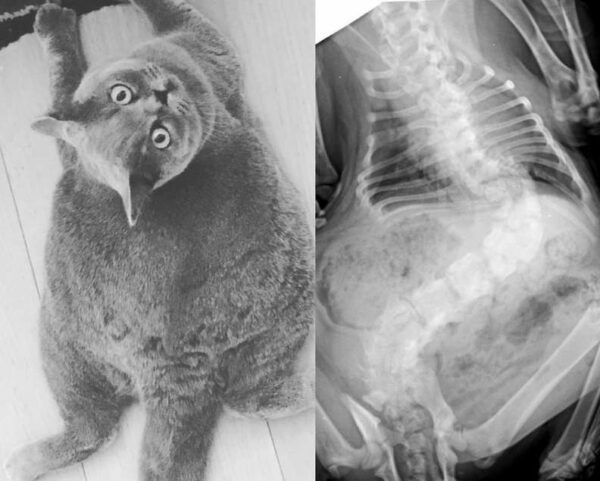

Pitoe’s story gained attention on Reddit recently when member Marie uploaded some photos and videos of him:

An x-ray of little Pitoe:

Due to her condition she finds it difficult to move or be teased by other cats. While she holds a strict day because of her weight

Pitoe is currently around four years old and living happily with her owners. Recently, an Instagram account was created in her honor, so that people may view her adorable photographs and follow her daily existence. “She has scoliosis, which gives her body its round form, but she is pain-free and happy!” her Instagram bio states. She belongs to my grandparents.”